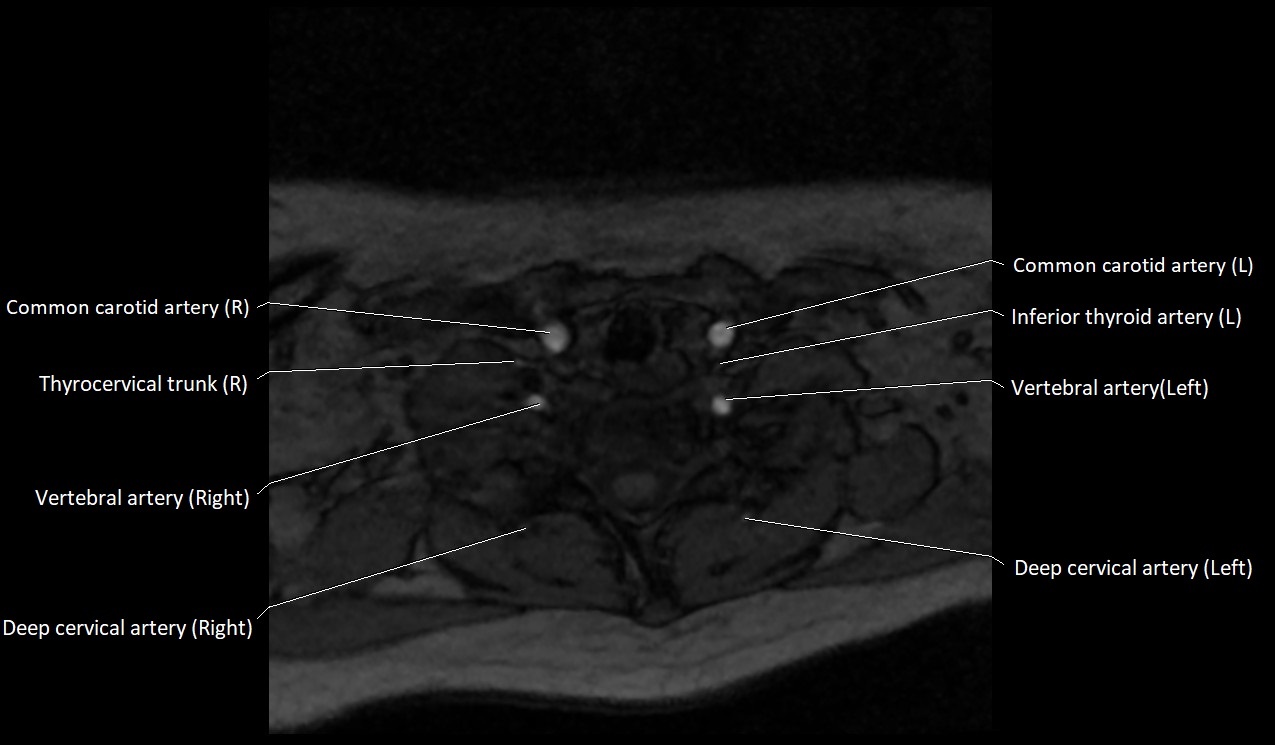

CT image

image